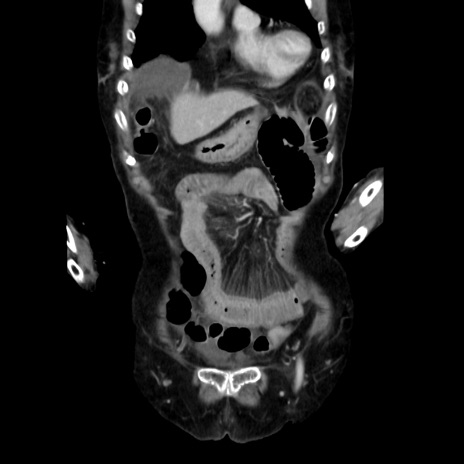

症例40(冠状断像)

【症例】90歳代女性

【主訴】腹痛・嘔吐

【現病歴】 食欲低下、嘔吐があり昨日他院受診。肺炎と診断され入院となる。入院後より腹部全体に圧痛あり。胃管留置され経過みていたが、症状持続するため、

当院転院となる。

【既往歴】胸椎圧迫骨折、胆石症

【身体所見】腹部:中央に激痛あり、圧痛あり、反跳痛不明

【データ】WBC 17100、CRP 18.82

矢状断像